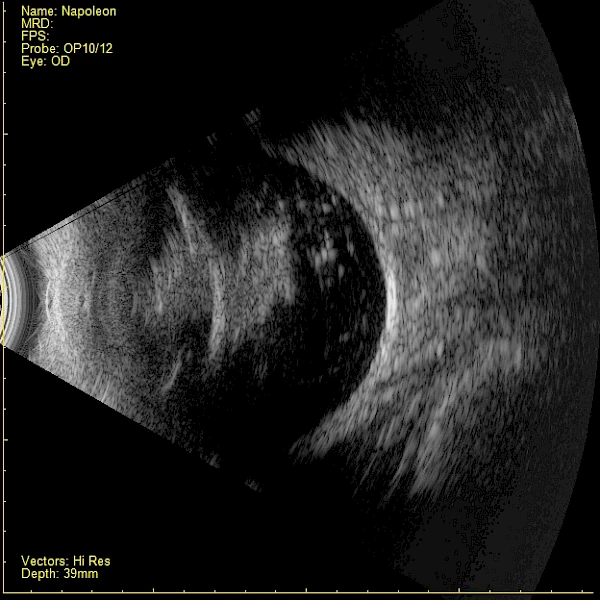

Ultraschallbild eines Hundes mit gerissener Hintere Linsenkapsel und Material im Glaskörper  und Netzhautablösung Ultraschallbild eines Hundes mit gerissener Hintere Linsenkapsel und Material im Glaskörper und Netzhautablösung